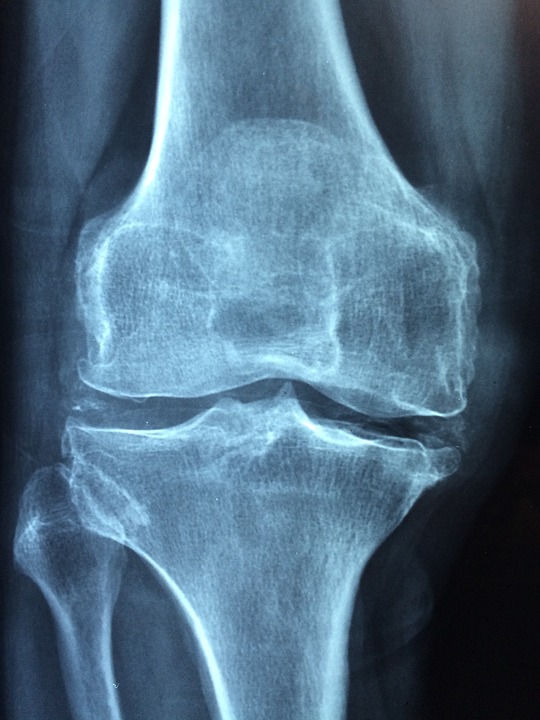

Her symptoms were suggestive of osteoarthritis. She had taken anti-inflammatory drugs & painkillers but only temporary relief.

Symptoms of Osteoarthritis [1]

Osteoarthritis is one of the most common chronic joint conditions seen in our clinics. Osteoarthritis is a non-inflammatory condition of joints that is characterised by progressive damage & loss of articular cartilage

disease progress pain become more of constant dull ache and sometimes become acute intense and sharp. Knee pain and stiffness become worse after prolonged inactivity or rest, such as getting out of bed in the morning, getting up from sitting position. Pain also gets worse by walking, climbing stairs. There may be stiffness, muscle weakness, joint instability & feeling of warmth in the joint. Swelling around knee may be seen, caused by osteophytes (bony spurs) and extra fluid in the joint. Joint creaking or crunching felt throughout the range of movement. The patient often has an antalgic gait, knees become bent and bowed.